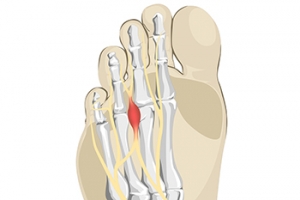

Some people feel the sensation of having a small pebble in their sock or shoe, and this can be a symptom of the foot condition known as Morton’s neuroma. It can develop as a result of wearing shoes that do have enough room in the toe area to move freely in. High heels can fall into this category and can affect women who frequently wear this type of shoe. This ailment affects the nerve between the third and fourth toes and can cause severe pain and discomfort. The nerve can become compressed and irritated, and mild relief may be felt when the shoes that are worn have a wider toe box. This condition will not improve when high heels are consistently worn, and surgery may be necessary to remove or repair the nerve. Patients may find some relief when anti-inflammatory medications are taken and the affected foot is massaged. If you have pain in this part of your foot, it is suggested that you visit a podiatrist who can diagnose and treat Moton’s neuroma.

Morton’s Neuroma

Morton's neuroma is a painful foot condition that commonly affects the areas between the second and third or third and fourth toe, although other areas of the foot are also susceptible. Morton’s neuroma is caused by an inflamed nerve in the foot that is being squeezed and aggravated by surrounding bones.

Morton's Neuroma

Morton's Neuroma, also called Intermetatarsal Neuroma or Plantar Neuroma, is a condition that affects the nerves of the feet, usually the area between the third and fourth toe. Neuroma refers to a benign growth that can occur in different parts of the body. Morton's Neuroma strictly affects the feet. This condition causes the tissue around the nerves that lead to the toes becoming thick, causing pain in the ball of the foot.

This condition can be caused by injury, pressure or irritation. Normally no lump will be felt, but instead burning pain in the ball of the foot will be experienced. Numbness and tingling may also occur. With the onset of this condition, a person may feel pain when tight or narrow shoes are worn. As the condition worsens, the pain may persist for days, or even weeks.

Persistent foot pain should always be a concern. The foot should be examined by a podiatrist if pain persists longer than a few days with no relief from changing shoes. The earlier the foot is examined and treated, the less chance there will be for surgical treatment.

There are some factors that can play a role in the development of Morton's Neuroma. These include wearing ill-fitting shoes that cause pressure to the toes, such as high heels. Also, high impact exercise may contribute to the cause of this condition. Morton’s Neuroma may also develop if the foot sustains an injury. Another cause includes walking abnormally due to bunions or flat feet. This causes excessive pressure and irritates the tissue. At times, people are affected for no determinable reason.

Podiatrists can alleviate the effects of this condition using a treatment plan to help decrease the pain and heal the foot tissue. Depending upon the severity of the Morton's Neuroma, the treatment plan can vary. For cases that are mild to moderate, treatments may include applying padding to the arch to relieve pressure from the nerve and reduce compression while walking. Ice packs can also help reduce swelling. The podiatrist may also create a custom orthotic device to support the foot and reduce compression and pressure on the affected nerve. The doctor will probably advise against partaking in activities that cause constant pressure on the affected area. They may provide wider shoes to ease the pressure from the toes. If these treatments do not relieve the symptoms of this condition, the doctor may use injection therapy.

Surgical treatment may be recommended by the podiatrist if all other treatments fail to provide relief. Normally, the podiatric surgeon will decide on either a surgical procedure that involves removal of the affected nerve or will choose surgery to release the nerve. After examination, the surgeon will decide on the best approach to treat the problem.

Recovery varies according to the type of surgical procedure. The patient will also be instructed on the best shoe wear to prevent the return of this condition, along with changes to workout routines, if this was a cause. Preventative measures are important in ensuring the condition does not return.